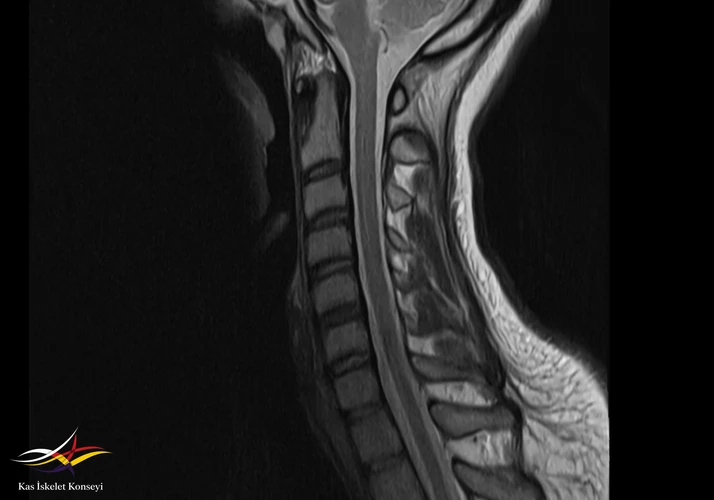

Servikal MR: C5-6 minimal bulging.

Resim 1. Servikal MRG: Normal.

Sevikal ve kol MRG normal olarak değerlendirildi. Brakial pleksus MRG optimal bulunmadı.